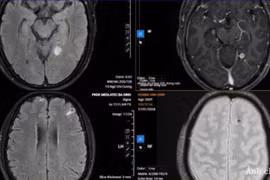

Người đàn ông vào viện vì thường xuyên đau đầu, chóng mặt, đau mỏi cơ đùi phải. Chiếu chụp phát hiện bệnh nhân nhiễm nhiều loại ký sinh trùng rải rác khắp cơ thể.

Kết quả chụp CT não cho thấy có 5 ổ sán nằm rải rác trong não, trong đó có một ổ sán lớn trên đỉnh đầu của bệnh nhân gây phù não. Bệnh nhân được chỉ định phẫu thuật gấp.